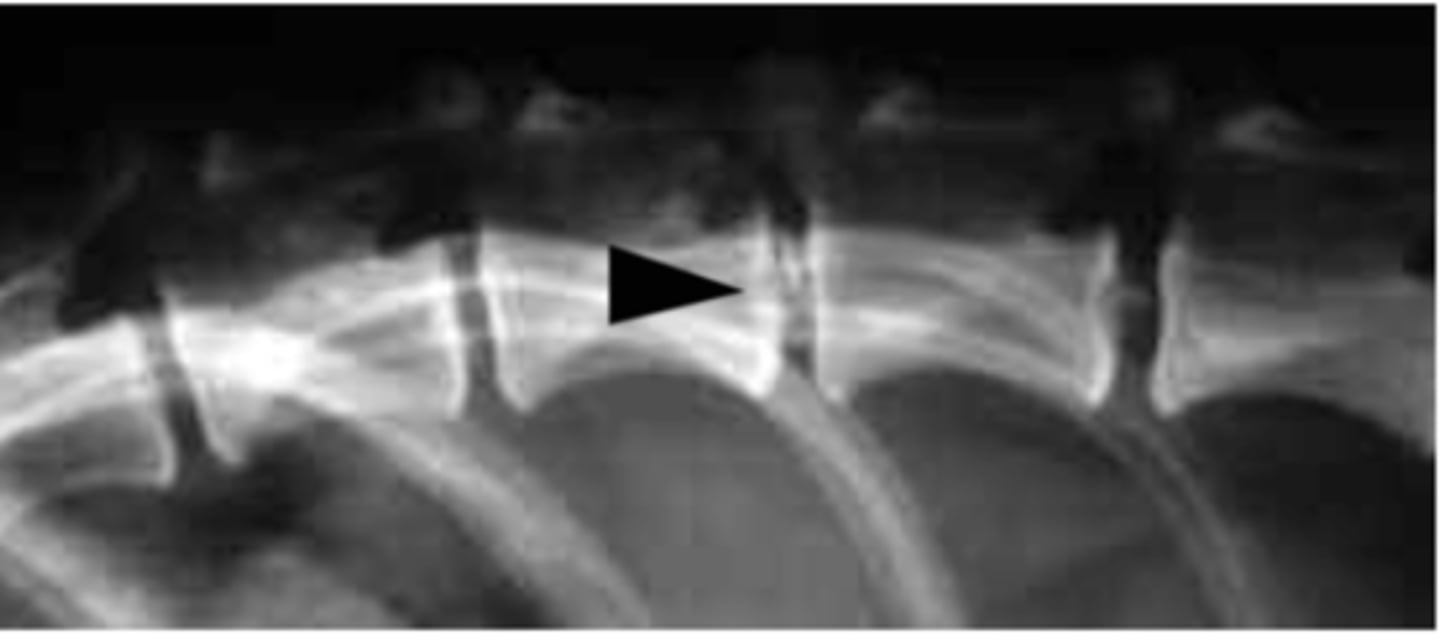

Mineralization of intervertebral discs

What is going on with this radiograph?

narrowed intervertebral space

What is seen in IVDD?